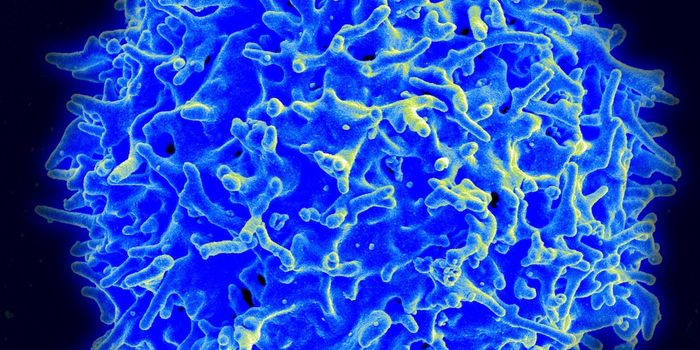

AUG 24, 2020ImmunologyOnce in the body, HIV tracks down T cells that bear the CD4 receptor. It attaches to these immune cells, fusing itself w ...